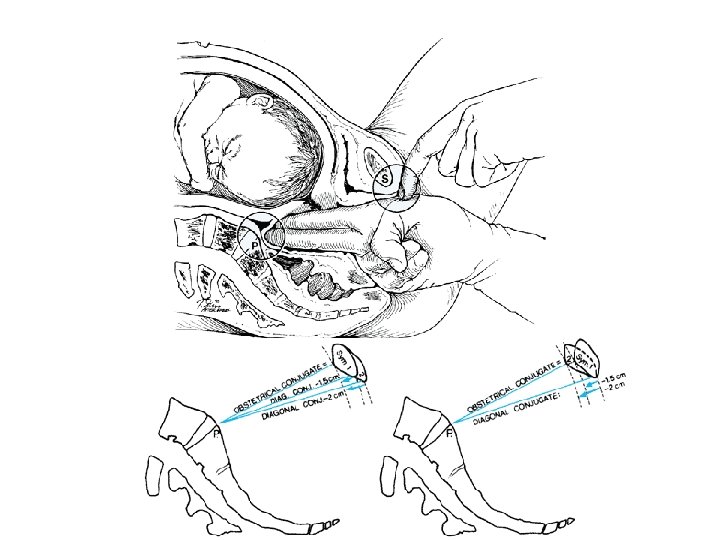

• Anatomical antero-posterior diameter (true conjugate) = 11 cm • Obstetric conjugate = 10. 5 cm (-2 cm from diagonal conj) • Diagonal conjugate = 12. 5 cm